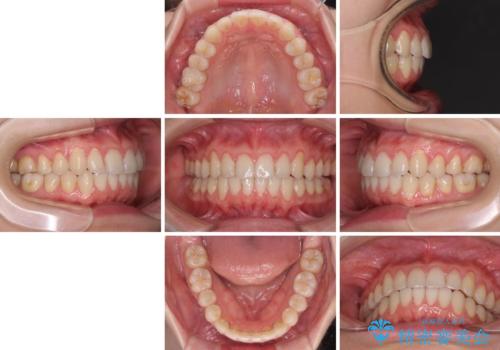

前歯のデコボコを治したい インビザラインによる矯正治療

- 上下前歯のデコボコを気にして来院された患者様です。

インビザラインによる上下歯列の側方拡大と後方移動、IPR(歯と歯の間を削る)にるスペースの獲得により歯列を整えることとしました。

1日22時間の装着時間をしっかり守ってくださったので、予定していた1年よりも早く治療を終えることができました。

インビザライン矯正特有の奥歯がしっかりと咬合しない感覚も改善され、大変満足していただきました。